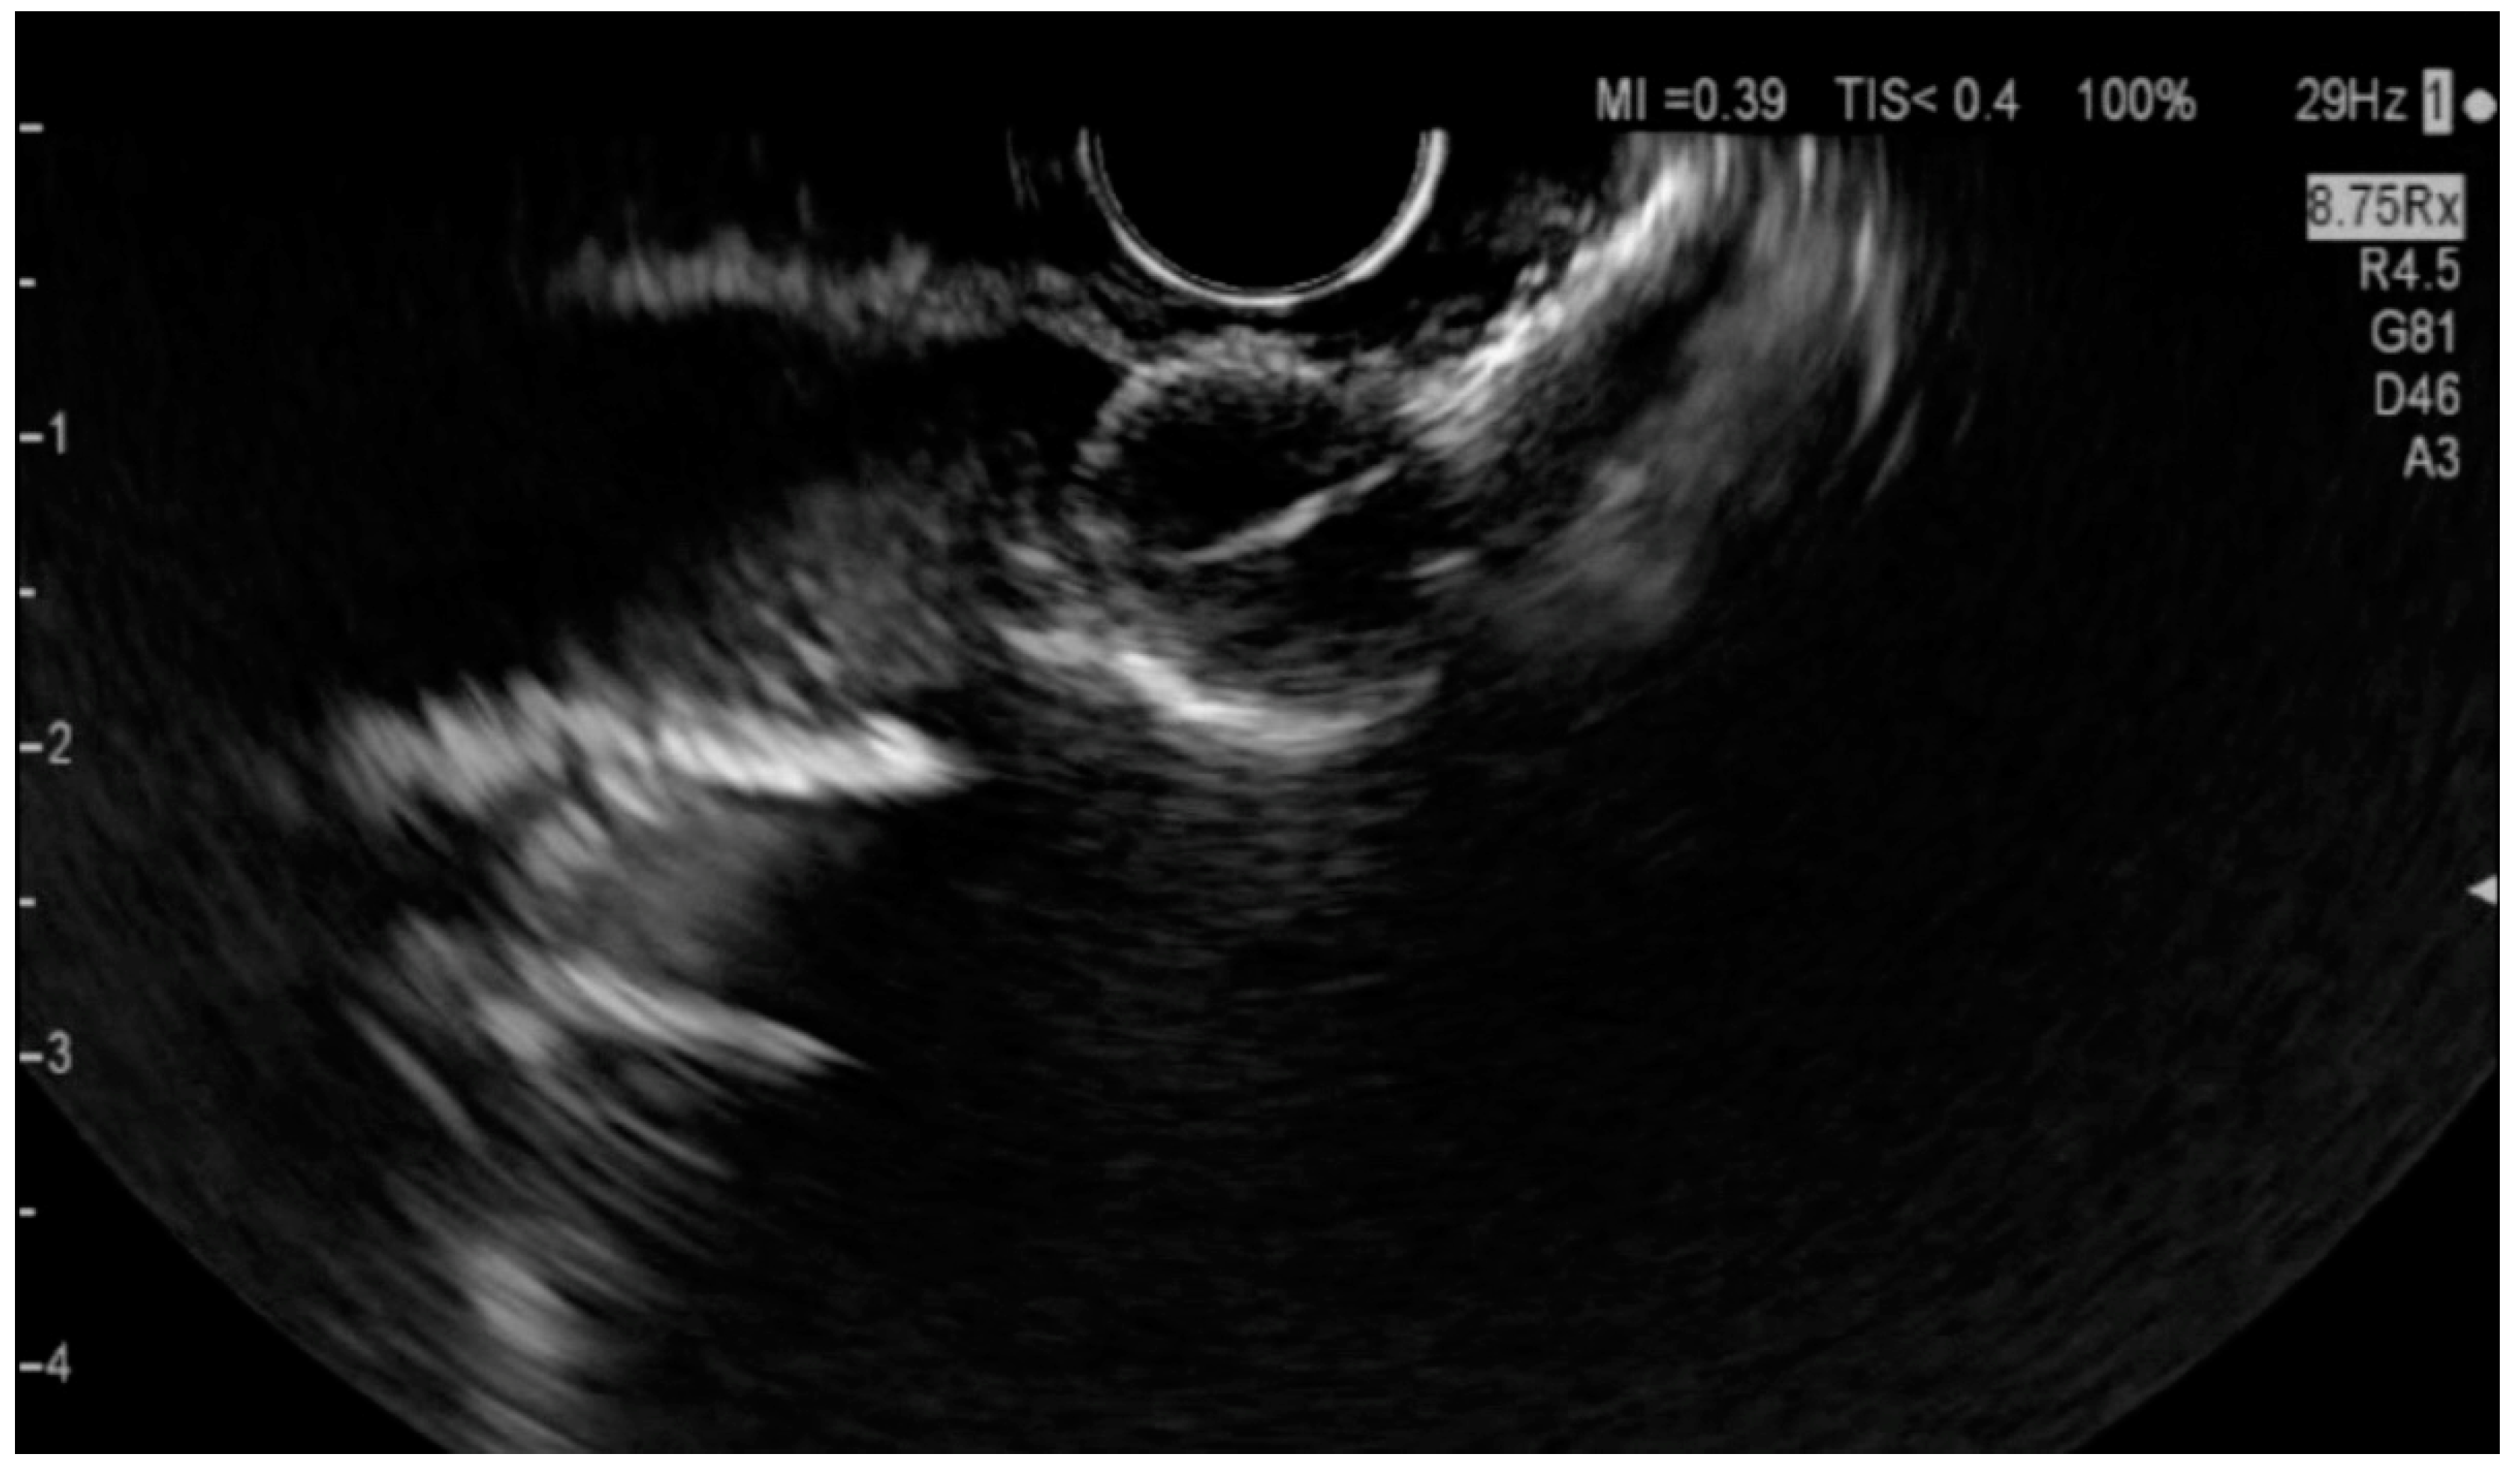

6.4.1. Endoscopic Ultrasound (EUS)

- Orzan, R.I.; Pojoga, C.; Agoston, R.; Seicean, R.; Seicean, A. Endoscopic Ultrasound in the Diagnosis of Extrahepatic Cholangiocarcinoma: What Do We Know in 2023? Diagnostics 2023, 13, 1023. [Google Scholar] [CrossRef] [PubMed]

- Otsuka, Y.; Kamata, K.; Hyodo, T.; Chikugo, T.; Hara, A.; Tanaka, H.; Yoshikawa, T.; Ishikawa, R.; Okamoto, A.; Yamazaki, T.; et al. Utility of contrast-enhanced harmonic endoscopic ultrasonography for T-staging of patients with extrahepatic bile duct cancer. Surg. Endosc. 2022, 36, 3254–3260. [Google Scholar] [CrossRef] [PubMed]

- Strongin, A.; Singh, H.; Eloubeidi, M.A.; Siddiqui, A.A. Role of endoscopic ultrasonography in the evaluation of extrahepatic cholangiocarcinoma. Endosc. Ultrasound 2013, 2, 71–76. [Google Scholar] [PubMed]